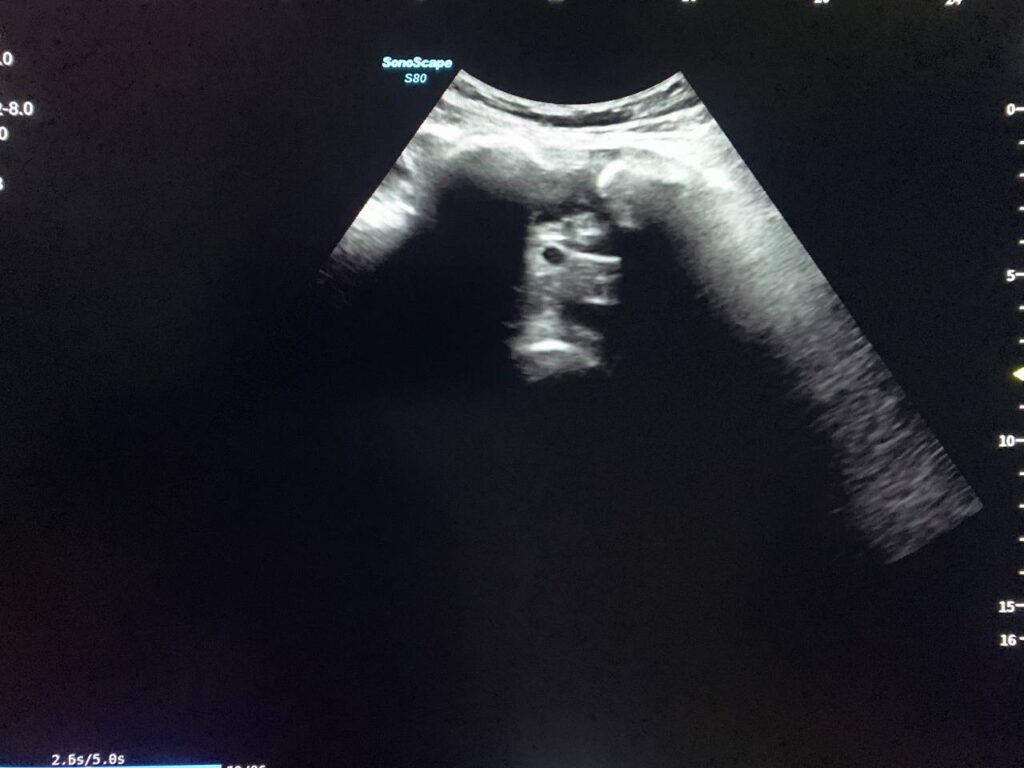

Right adnexa contain heterogenous calcified mass >75x56mm & other lobulated calcified mass >100x66mm seen in the left adnexa , picture mostly of bilateral ovarian mature Terato-dermoid cysts , please for further study (Plain X-Ray of the pelvic for calcifications )

· Small amount of free pelvic fluid , history of recent surgery